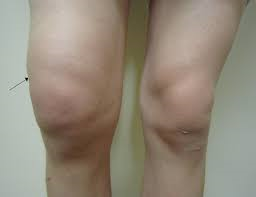

부종 및 물이 참: 관절 내부에 염증이 생기면서 무릎이 붓고, 관절액이 차는 현상이 나타날 수 있습니다.

관절 변형: 시간이 지나면 관절이 O자형(내반슬) 등으로 변형될 수 있습니다.